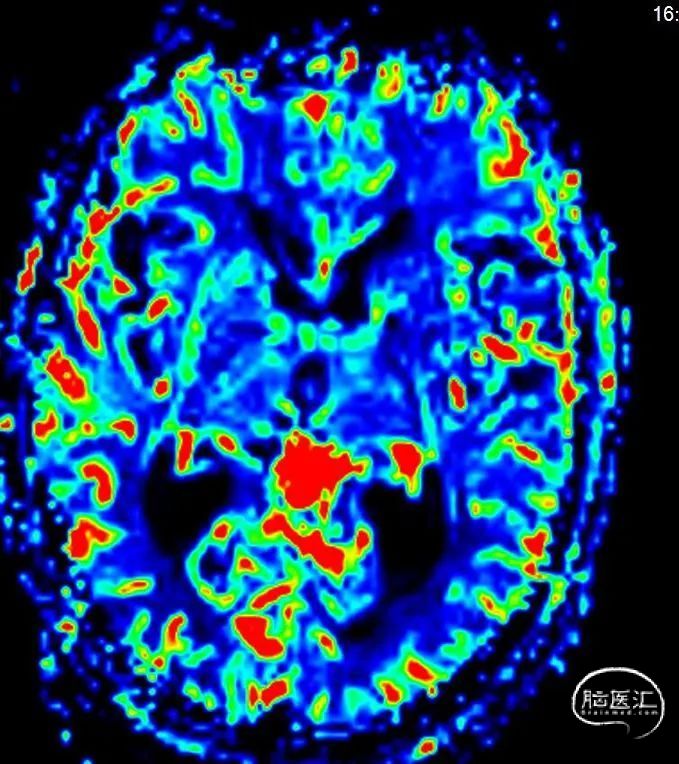

MR灌注

MTT

TTP

CBF

CBV